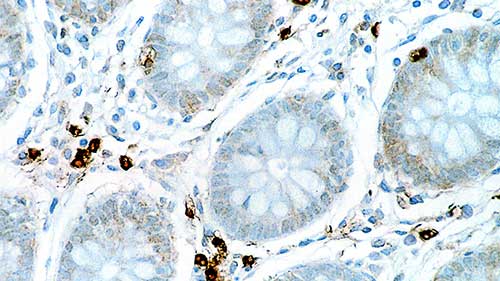

Human colon: immunohistochemical staining for Interleukin 6. Note cytoplasmic staining of a proportion of lymphoid cells. Interleukin 6: clone 10C12